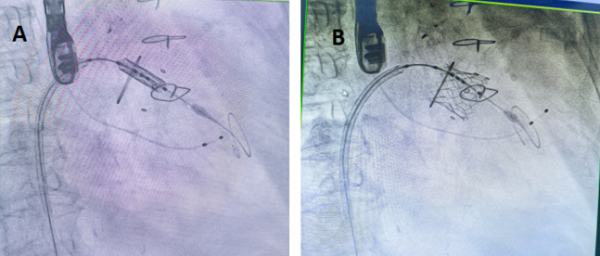

手术当天,团队为刘英芳开启了 “心门修复” 之旅。由右侧股静脉入路,使用房间隔穿刺器穿刺房间隔,开通股静脉-房间隔-左心房-左心室的通路,插入导丝和鞘管建立输送轨道。房间隔处进行预扩张处理,将预装好瓣膜的输送系统沿导丝推送至二尖瓣瓣环位置,在经食道超声实时指导下进行瓣膜的精准定位。快速起搏,待血压降至50mmHg以下充盈球囊实现瓣膜的释放。

手术过程:A.瓣膜定位;B.瓣膜释放;